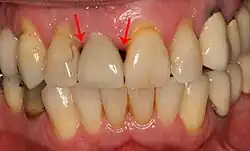

Aby implantát vypadal esteticky, je navíc zapotřebí, aby prostor po obou stranách implantátu vyplnil pruh plné, kypré dásně. Nejčastější komplikací měkkých tkání je tzv. černý trojúhelník, kdy se trojúhelníkový kousek tkáně mezi dvěma zuby ( papila) smrští. Mezi implantátem a sousedními zuby tak vznikne trojúhelníková mezera. Zubní lékaři mohou očekávat pouze 2–4 mm výšky papily nad podkladovou kostí. Pokud je vzdálenost mezi místem, kde se zuby dotýkají, a kostí větší, lze očekávat černý trojúhelník.[29]:s.81-84